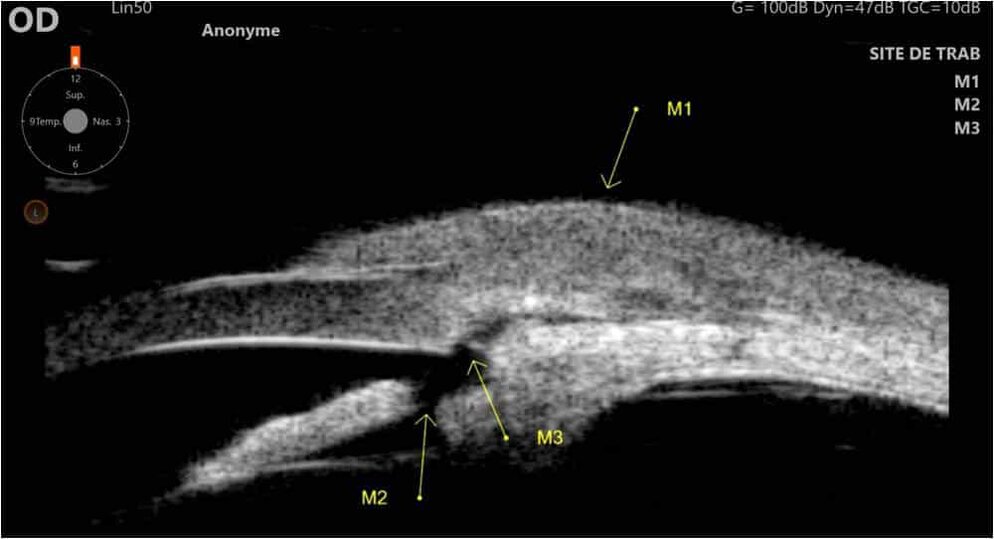

Figure 4 : Œil droit : Site de trabéculectomie visible en biomicroscopie ultrasonore (UBM).

(M1) Bulle de filtration (M2) site de trabéculectomie proprement dit (M3) iridectomie périphérique chirurgicale.